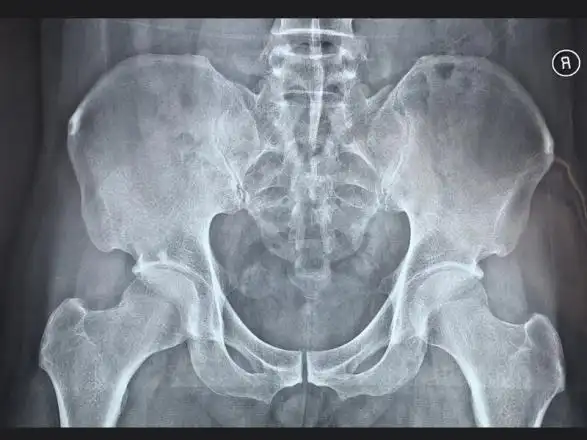

黔东南州人民医院黎平医院骨科顺利完成一例强直性脊柱炎的强直髋全髋